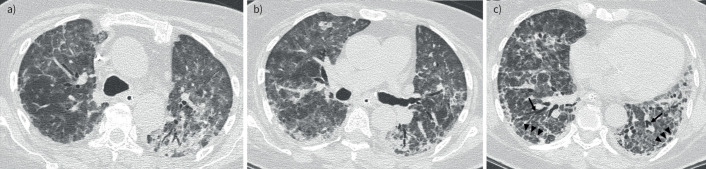

黏液表皮样癌是一种罕见的肺部原发性肿瘤。在仔细排除其他肺部肿瘤,尤其是那些组织学和放射学特征重叠的肿瘤后,可以做出诊断。https://bit.ly/4fcISSm。

Mucoepidermoid carcinoma is a rare primary tumour of the lung. Diagnosis can be made after careful exclusion of other lung neoplasms, especially those with overlapping histological and radiological features. https://bit.ly/4fcISSm.